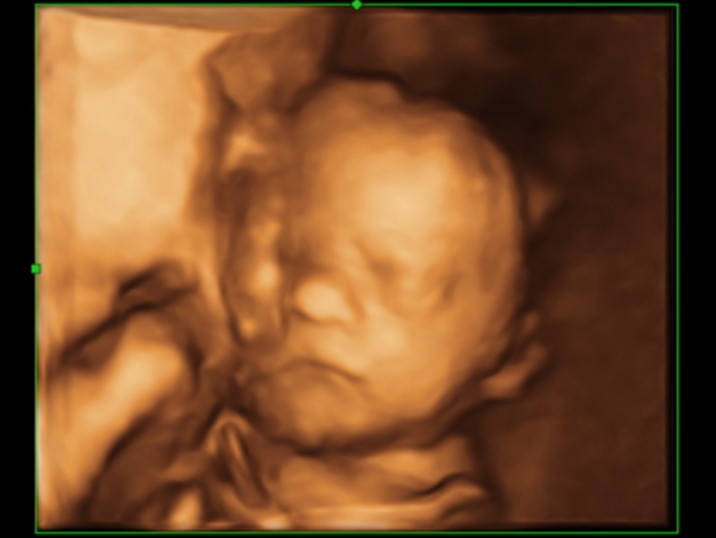

Скажите, это один и тот же малыш? Просто губки очень разные)) первые две фото очень похожи, прям один в один, и следующие две тоже очень похожи))

😂 😂 😂 Один и тот же, просто этот малыш губки свои шикарные пожимать любит иногда во время сна! 😊 Он это делал в животике и когда родился - так же!

Нам когда сделали УЗИ мы обалдеи, что малыш на фото разный, а потом предположили, что губки поджимает и всё таки родится с пухленькими и бантиком! 😊 Так и вышло

Мы не давно на 27 неделе ходили тоже на 4D. Так как клиника частная то пустили с мужем без всяких проблем. Посмотрели на личико нашей доченьки😍 у мужа не сходила улыбка с лица.